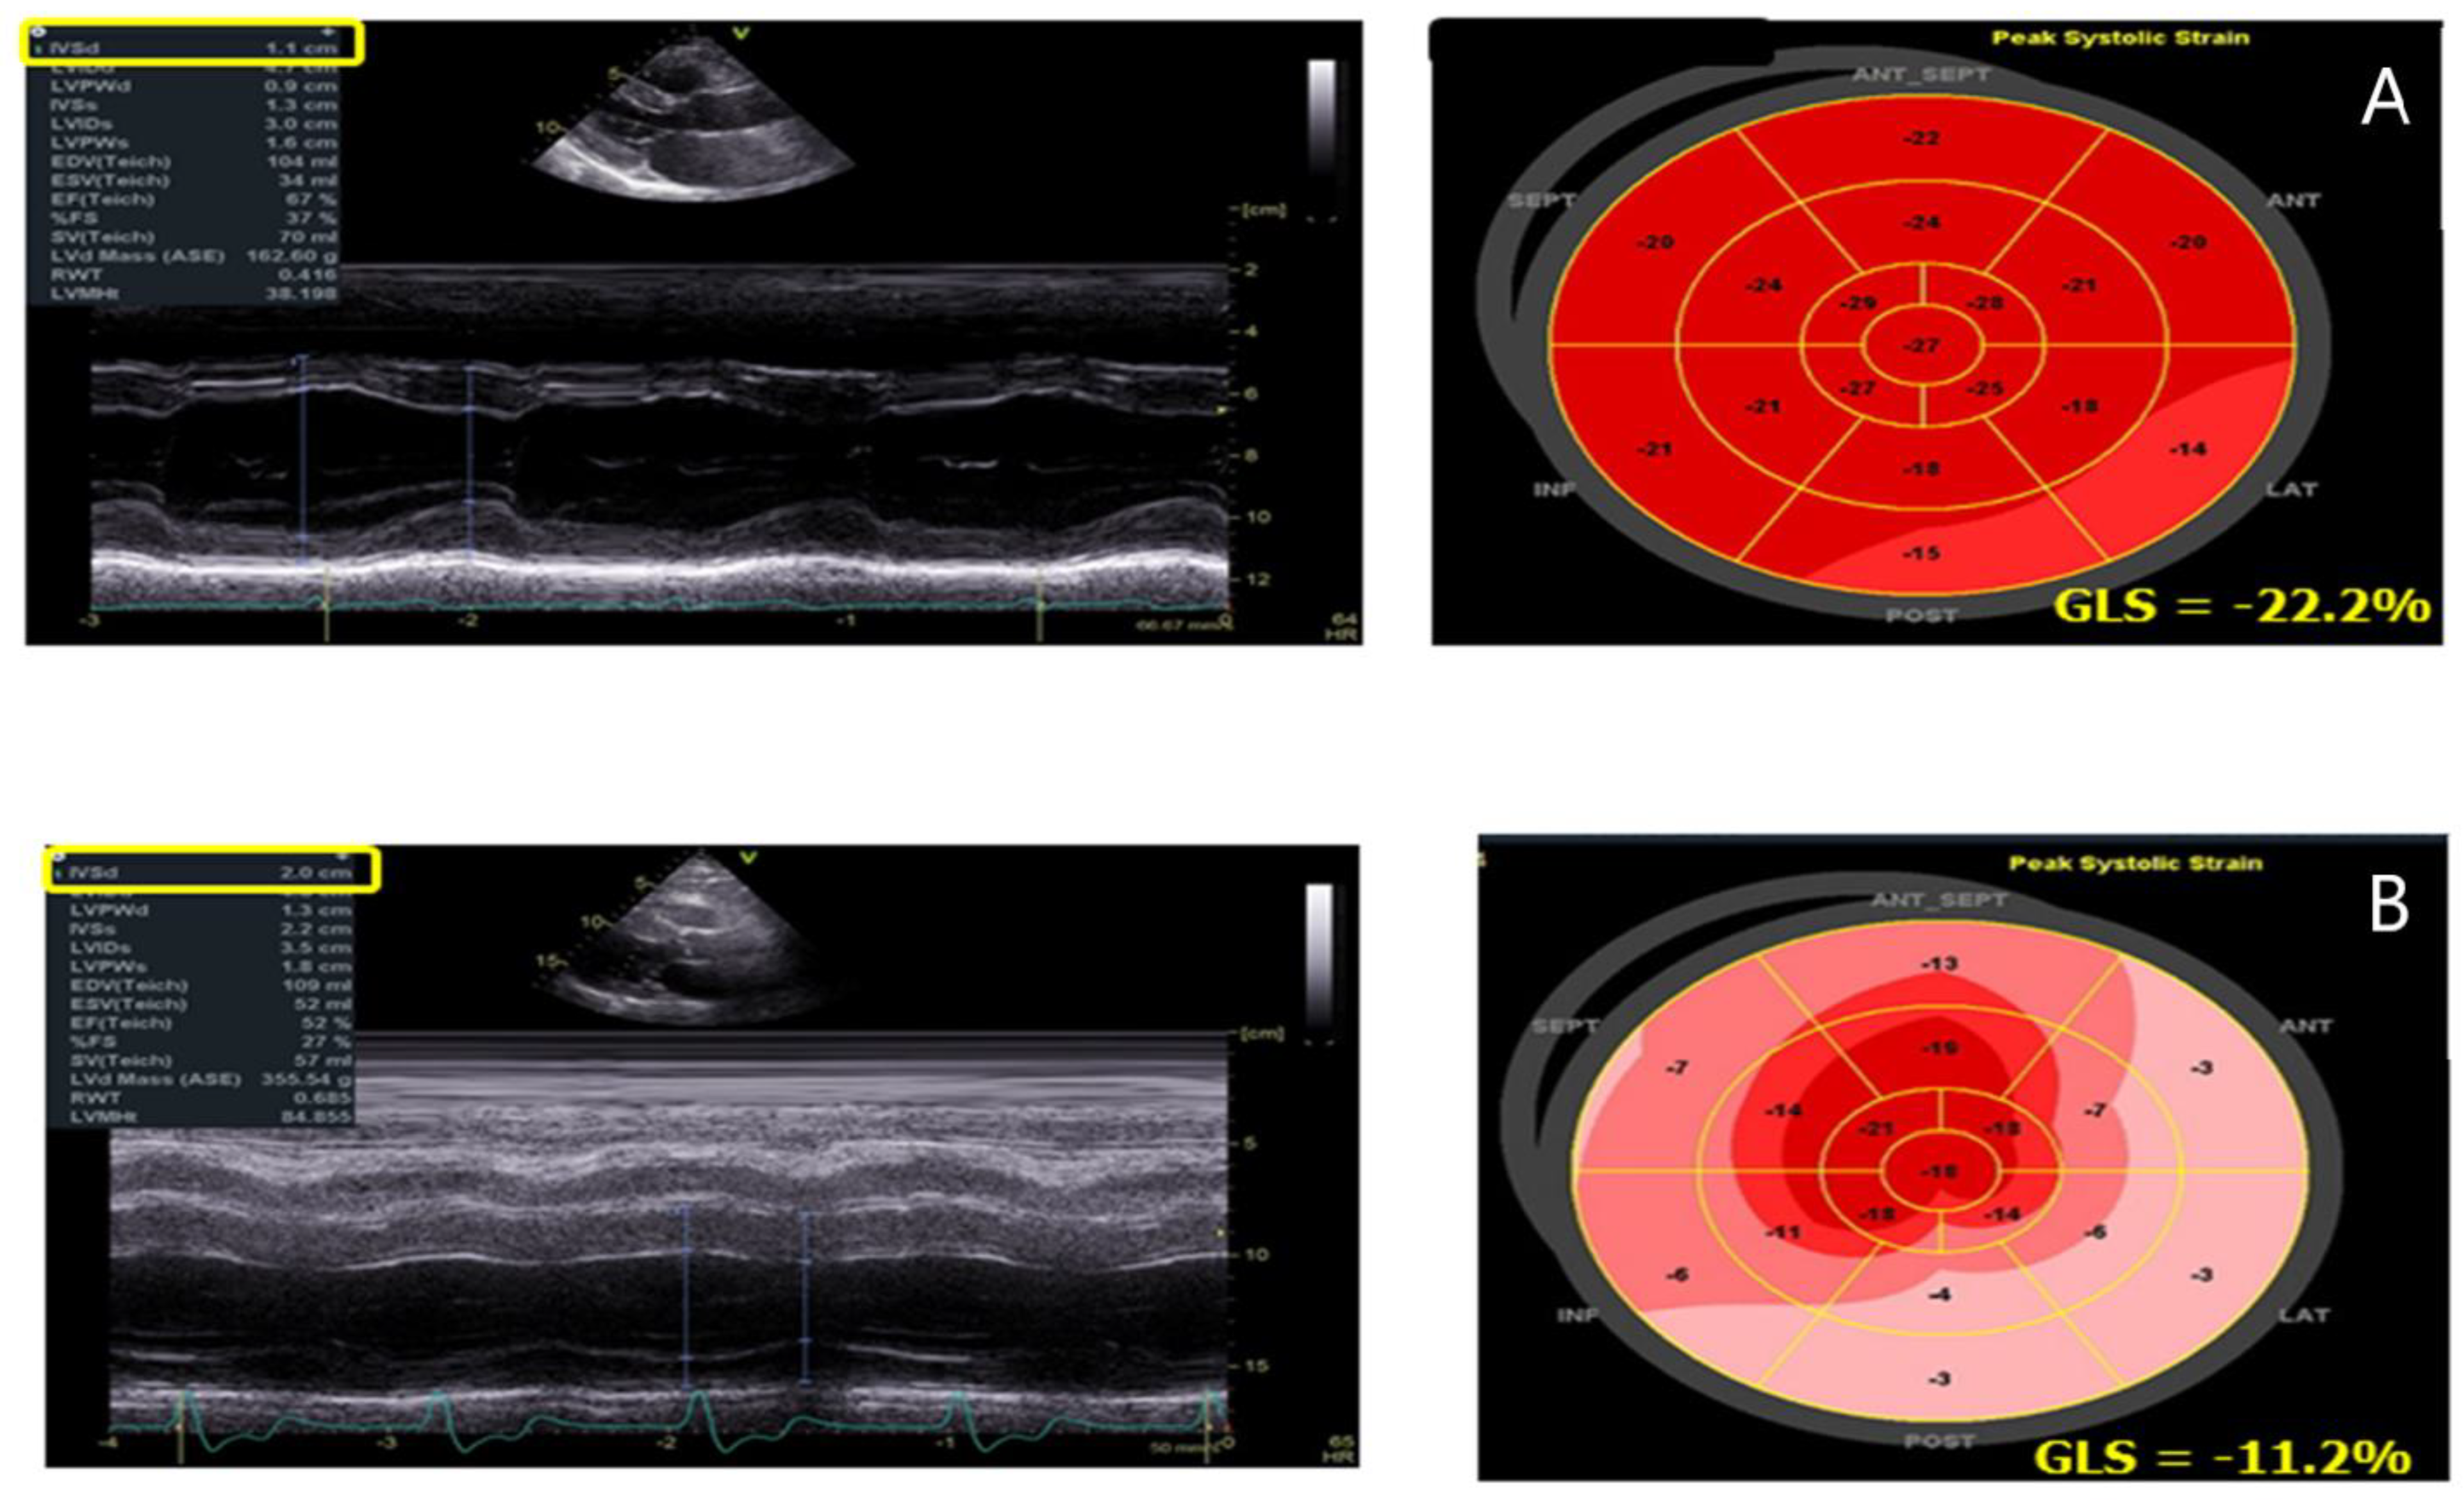

| GLS | -Reduction in LV GLS with a prevalent involvement of the infero-lateral wall of the LV | -Correlates with LGE at CMR |